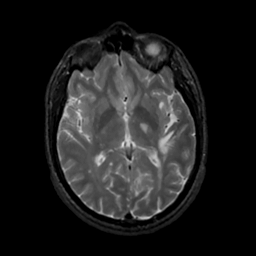

MR Study #7, March 24, 1991 -- Slice #25